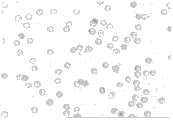

Fig. 5 is the normal morphology erythrogram that digital CCD takes.

Step 2: carry out the image information collection with 2 pairs of video camera or CCD elements marked region, Fig. 5, Figure 11, Figure 17 are the erythrogram that collects; The normal morphology red blood cell, the cell size is more consistent, and cell space is normal or bigger than normal, and haemoglobin is abundant, and no gemma forms, and cell membrane is complete.All kinds of parametric statistics curve maps are essentially normal distribution, and distributed areas are more concentrated.